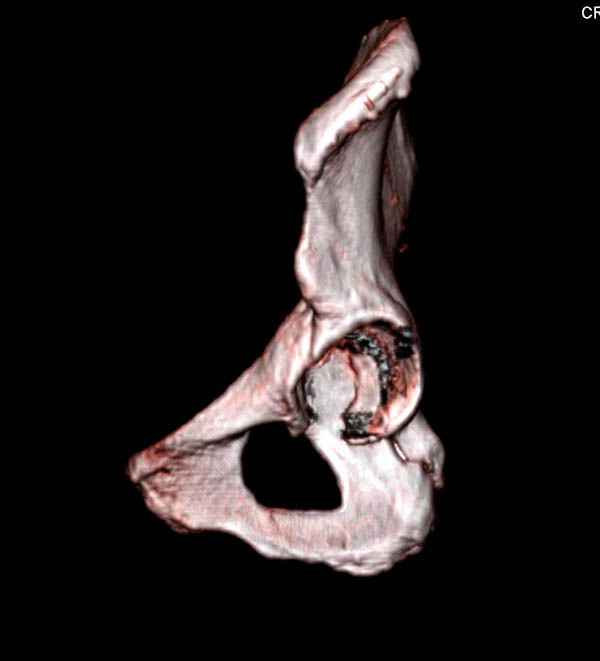

На снимке ацетабулума редко встречающийся очень низкий перелом, наверное, трудно было репозицию через один доступ? Перелом как бы замкнулся в квадрилатеральной поврехности.

Ничего такого особенного в переломе вертлужной впадины не опознал. Транстектальный перелом хорошо репонируется щипцами, установленными через седалищную вырезку.

На картинке подобный случай, только без шейки, сделано через месяц или полтора после травмы.